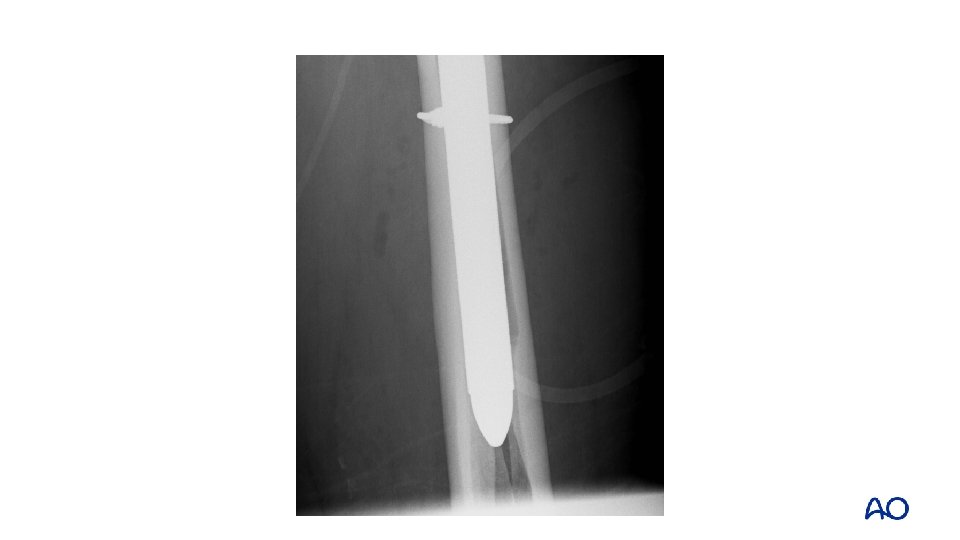

Case 7 • • • Proximal fracture through calcar and greater trochanter Uncemented stem with loss of fixation Vancouver B 2

Case 7 • • Fully coated long, straight stem Failure to ream full length of cylindrical stem

Case 7 • • Vancouver B 1 Fix without revision